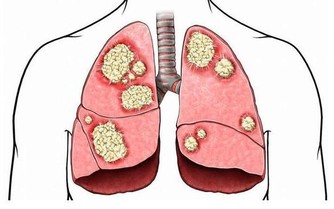

除此以外,才是胃的問題,比如胃食管反流、消化不良、幽門螺桿菌感染等。

如果經檢查(如抽血查抗體,作呼吸實驗、胃鏡等)確定是幽門螺桿菌感染所引起的口臭,可進行針對性抗菌治療,如使用抑酸藥、抗生素及鉍劑。

只要流程規範,效果一般都比較顯著。隨著菌量的下降,口臭自然會減輕。